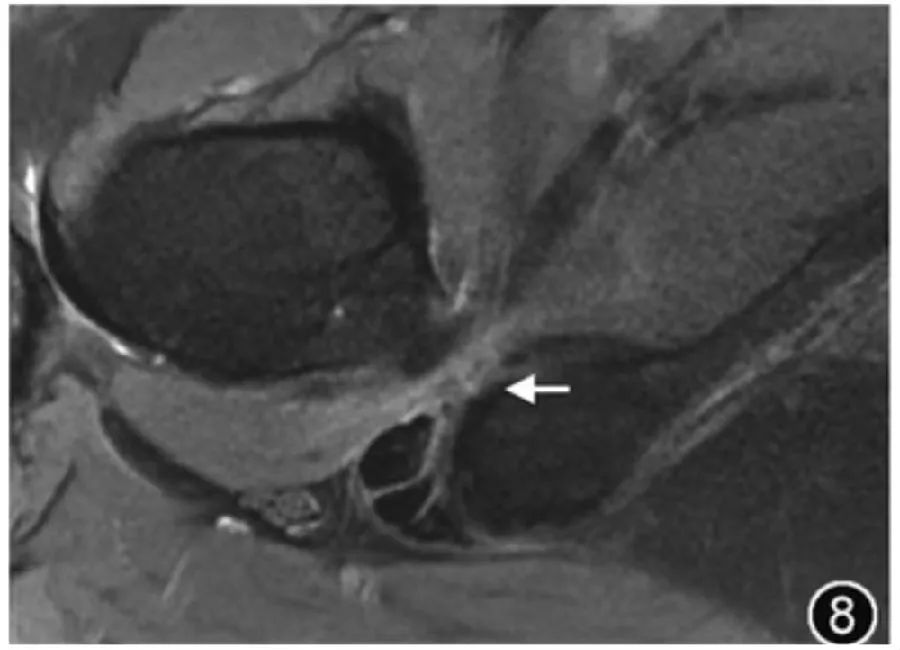

7.Ишофеморальный импинджмент-синдром: Ишофеморальный импинджмент-синдром вызван ущемлением квадратной мышцы бедра между малым вертелом и седалищным бугорком, вызывая глубокую боль в ягодицах из-за сужения седалищно-бедренного пространства. У пациентов с симптомами аномальное сужение седалищно-бедренного пространства и отек квадратной мышцы бедра с атрофией или без нее указывают на синдром седалищно-бедренного импиджмента. До сих пор существуют разногласия по поводу критического значения для определения сужения седалищно-бедренного пространства, что может быть связано с анатомическими различиями и разными методами измерения у людей в разных регионах. Однако обычно считается, что седалищно-бедренное пространство составляет <15 мм и/или квадратная мышца. Расстояние до бедра <10 мм, возникает перелом седалищной кости. Вероятность ущемления бедренной кости выше (рис. 8). Если наблюдается отек квадратной мышцы бедра при отсутствии сужения седалищно-бедренного пространства, седалищно-бедренный импинджмент не следует рассматривать и следует рассматривать как причину растяжения, разрыва или денервации квадратной мышцы бедра.

Рисунок 8. МРТ-изображение седалищно-бедренного воздействия. На поперечном срезе Т2-ВИ видно узкое бедренно-седалищное пространство шириной 6,4 мм, сопровождающееся отеком квадратной мышцы бедра (↑).